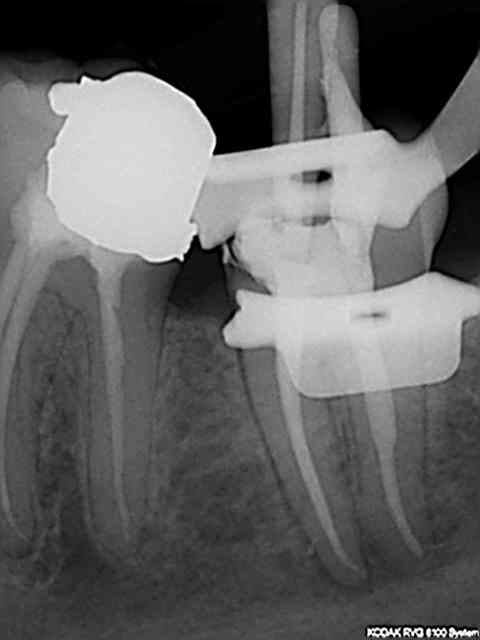

Tu crois que si je travaille sous dique et que je jette un r25 et un saf par pulpec et que je me fais chier à traiter les mv2 c'est pour mettre une bouse d'amalgame à 2 balles dessus ?